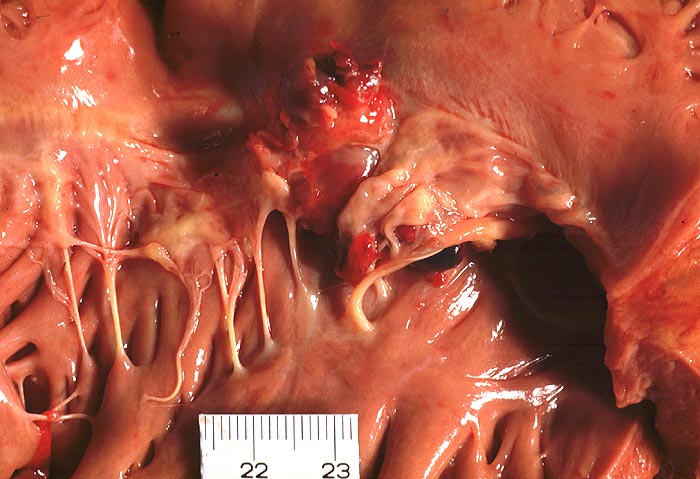

Basel 1MA/ Infektiöse Endocarditis ulcero-polyposa

Infektiöse Endocarditis ulcero-polyposa

Mitralklappe

Makroskopisch sind entweder flache rötliche fibrinbelegte Ulzera (=ulcerosa (> 2935)) oder zusätzlich weiche gelbbraune bröcklige erbs- bis pflaumengrosse Polypen (=ulceropolyposa (> 2936) (> 8376)) oder ausschliesslich polypoide Fibrinbeläge (=marantica) auf einem Endokarddefekt oder einer partiell zerstörten Klappe erkennbar.

Histologisch findet sich bei ulzeropolypöser Endokarditis ein Fibrin-Thrombozytenthrombus, welcher von Bakterien durchsetzt ist (=Vegetation). Die Vegetation sitzt auf einem Klappendefekt an dessen Basis Granulationsgewebe einzusprossen beginnt, welches den Thrombus organisiert. Klappendefekte, Gefässeinsprossungen, verdickte Sehnenfäden (> 2848) oder Kommissurenverwachsungen (> 8389) der Taschenklappen weisen morphologisch auf eine abgeheilte Endokarditis hin.

Mögliche Komplikationen einer infektiösen Endokarditis sind Klappenperforation (> 2934) oder Sehnenfadenruptur mit akuter Klappeninsuffizienz, Klappenstenose durch grosse Vegetationen, Übergreifen der Entzündung auf das Myokard, Dehiszenz von Klappenprothesen, Klappenvitium, Sepsis, septische (> 2120) oder sterile, häufig zerebrale Embolien, mykotisches Aneurysma und Glomerulonephritis.